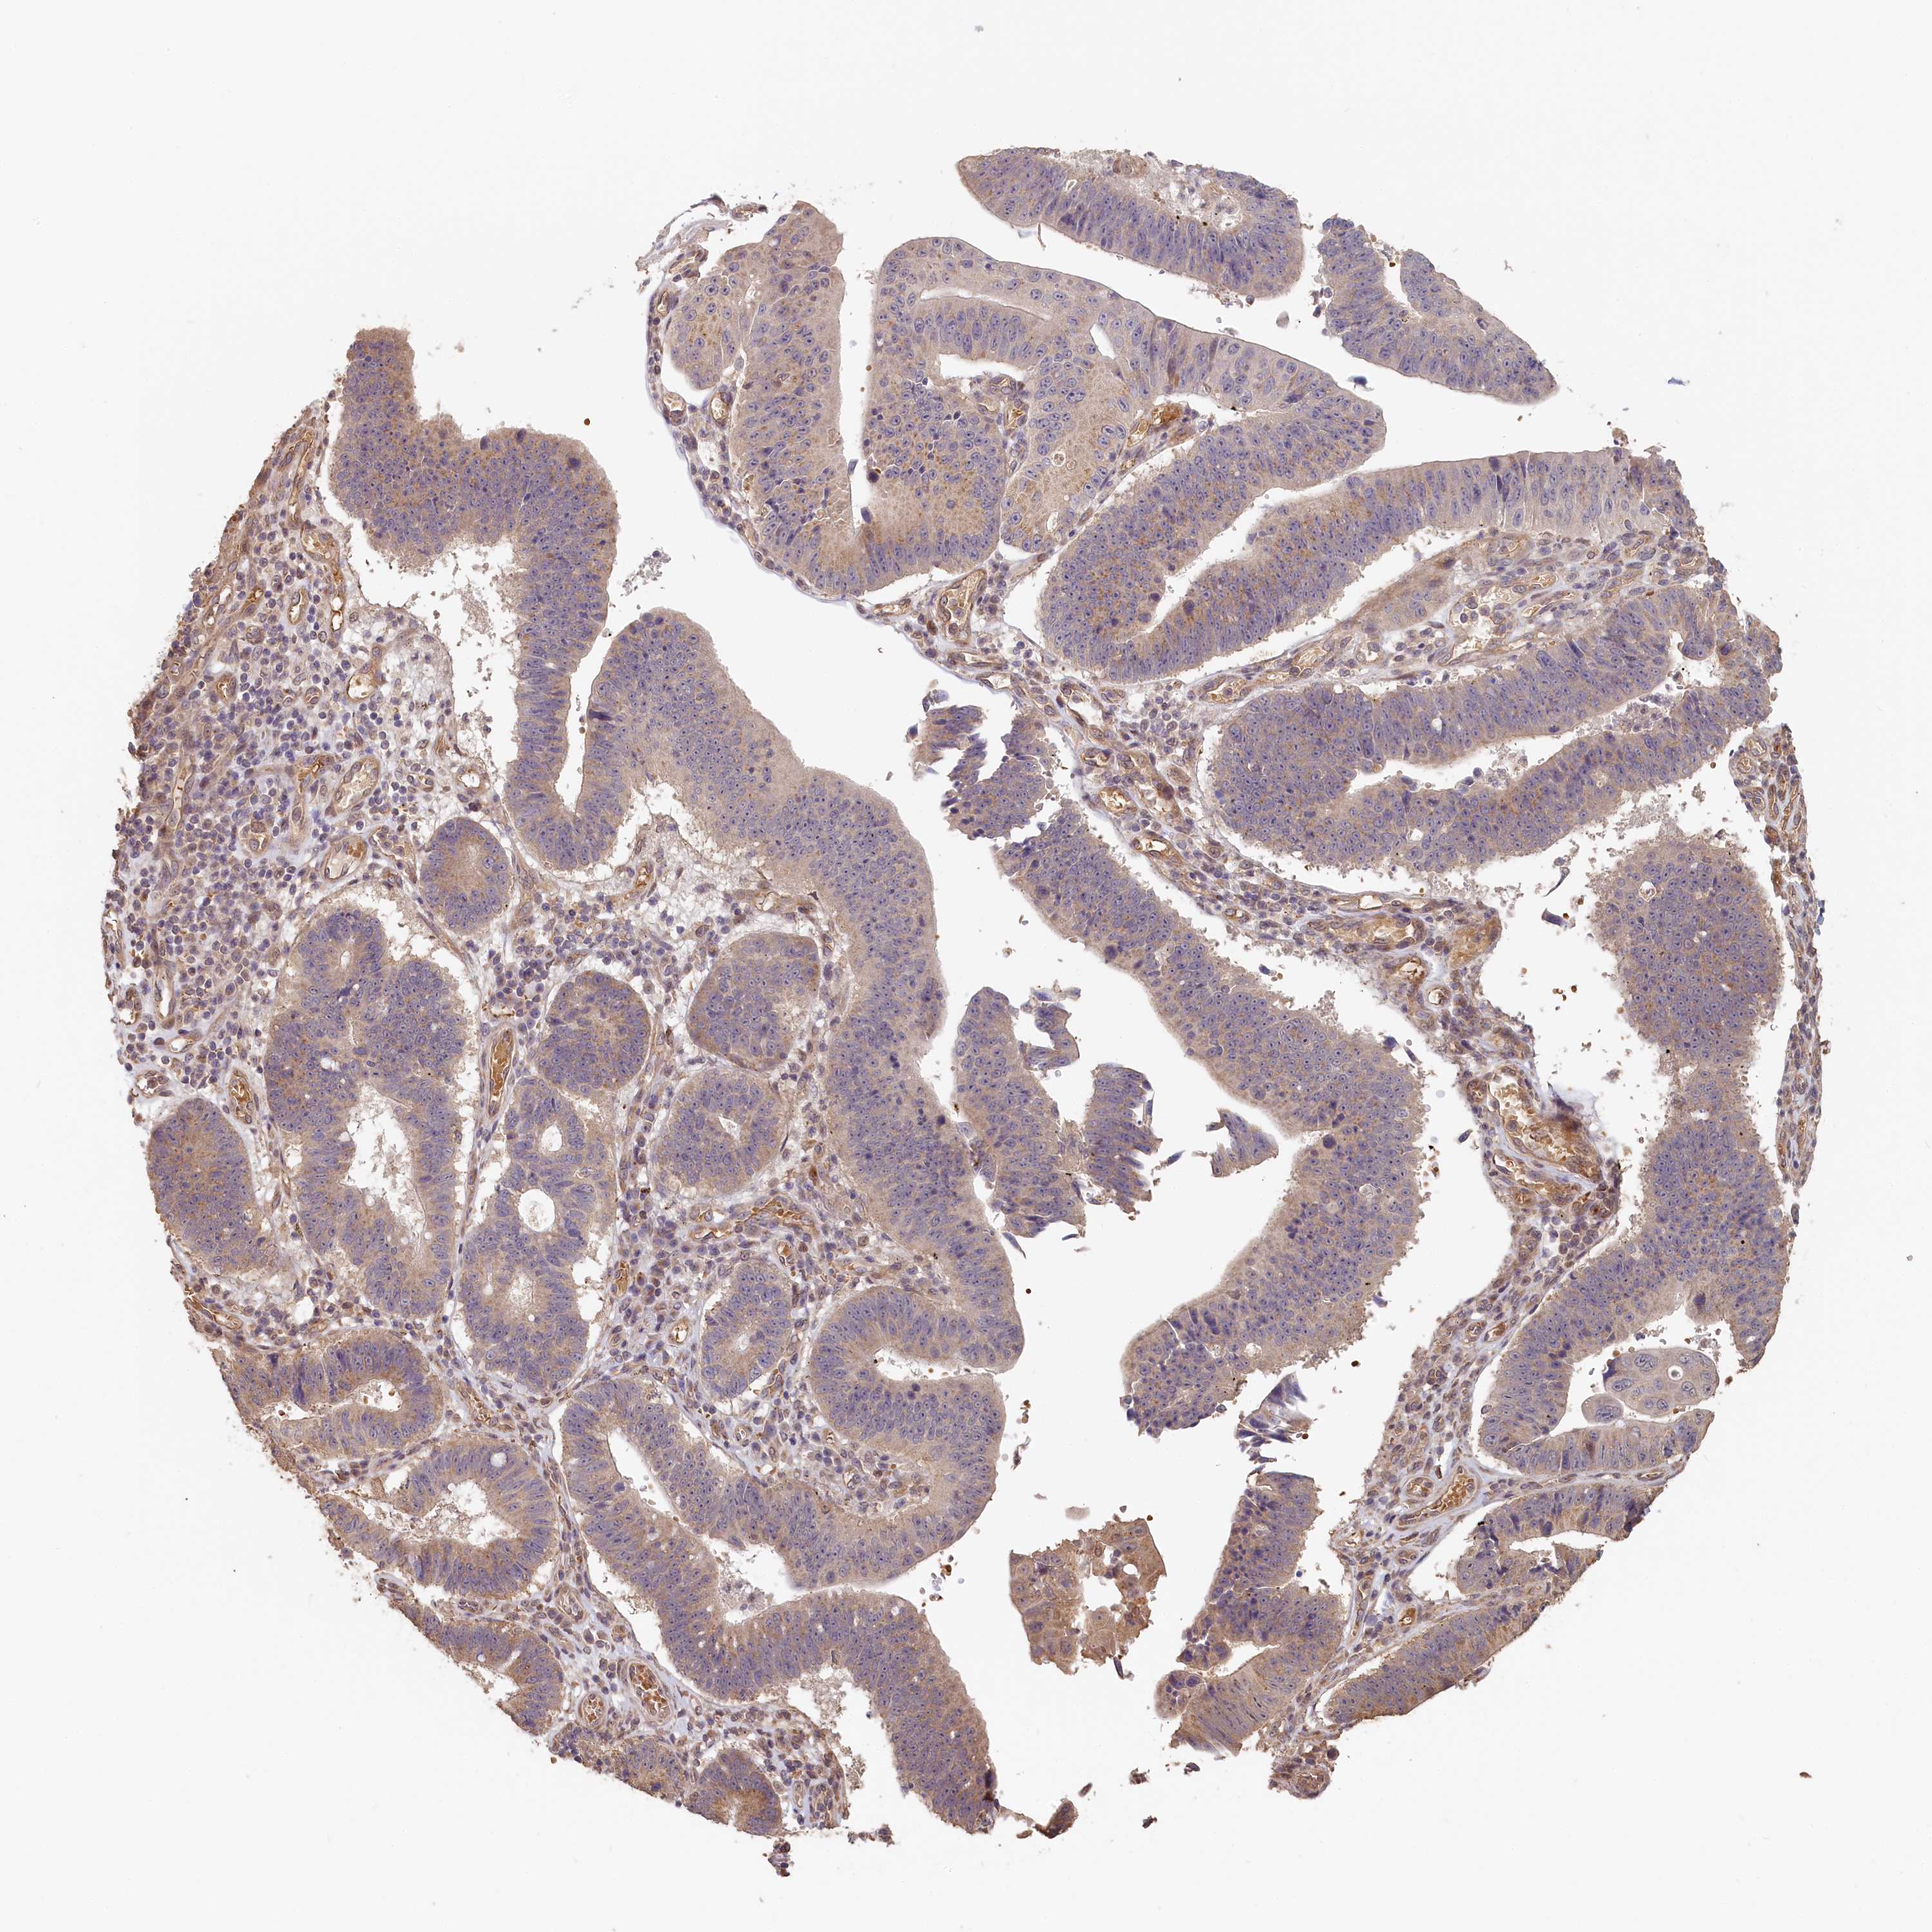

STOMACH CANCER - Protein expressioni

A mouse-over function shows sample information and annotation data. Click on an image to view it in a full screen mode. Samples can be filtered based on level of antibody staining by selecting one or several of the following categories: high, medium, low and not detected. The assay and annotation is described here.

Note that samples used for immunohistochemistry by the Human Protein Atlas do not correspond to samples in the TCGA dataset.

Antibody stainingi

Antibody staining in the annotated cell types in the current human tissue is reported as not detected, low, medium, or high, based on conventional immunohistochemistry profiling in selected tissues. This score is based on the combination of the staining intensity and fraction of stained cells.

Each image is clickable and will lead to virtual microscopy that enables deeper exploration of all samples and also displays staining intensity scores, fraction scores and subcellular localization as well as patient and tissue information for each sample.

Antibody HPA041019

Antibody HPA042033

Staining

High

Medium

Low

Not detected

Intensity

Strong

Moderate

Weak

Negative

Quantity

>75%

75%-25%

<25%

None

Location

Nuclear

Cytoplasmic/membranous

Cytoplasmic/membranous,nuclear

Adenocarcinoma, NOS